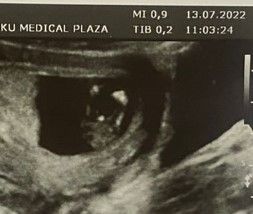

Не очень понятно пока, но кажется, что мальчик.

Думаю, девочка. У моего торчал прям перпендикулярно половой бугорок.

Мне кажется, что девочка!) А врач не предположил?

Половой бугорок не видно. Второе фото не информативно (между ножек на таком сроке не смотрят).

Мне кажется что у Вас на фото вообще не видно полового бугорка, и ещё мне кажется что малыш сосёт ногу)

На девочку похоже